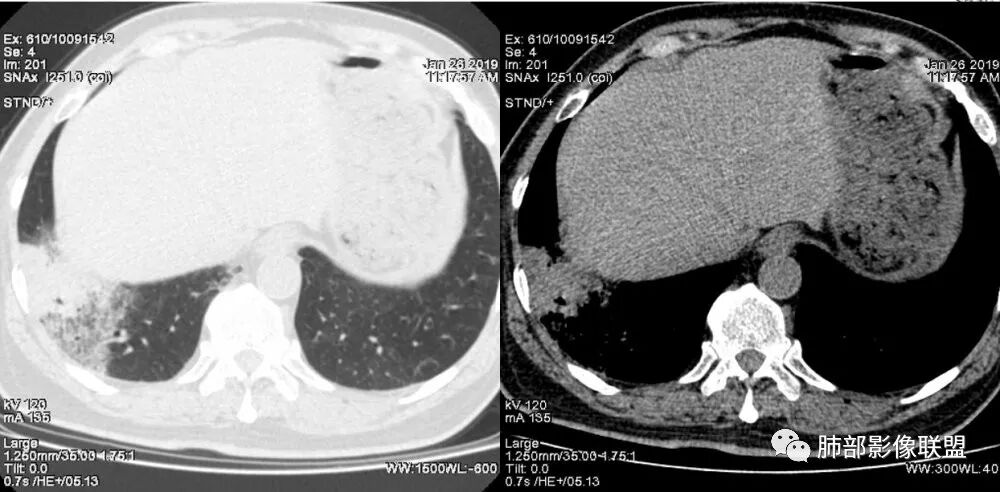

老年女性,右肺下叶沿胸膜下大片状高密度影,外周磨玻璃影,边界较清,内可见蜂窝征及支气管充气征,考虑肺炎型肺癌。

老年女性,咳嗽咳痰病史,右肺下叶大片磨玻璃实变影,胸膜下分布,支气管进入后扩张、僵直,磨玻璃影边界清楚,考虑粘液腺癌。鉴别肺炎。

右肺下叶基底段靠胸膜实变/磨玻璃混杂密度影,边界清楚,内见多发空泡(蜂窝样趋势改变?); 临床:咳嗽咳痰,无发热、胸痛; 考虑腺癌:无发热,感染性病变不首先考虑;部分层面形态类楔形,鉴别肺栓塞

老年女性,右下肺实变影,病灶里有小叶内间质增厚,周围GGo,支气管扩张,粘液性腺癌?淋巴瘤?

中年女性,咳嗽咳痰。右肺下叶片状高密度影,部分实性密度,周围见边界清晰磨玻璃影,内见小空泡,实性区部分支气管堵塞,有重力效应,考虑肺炎型肺癌,建议查痰脱落细胞。

老年人,右肺下叶斑片状阴影,病灶有膨胀性,边缘可见磨玻璃影,其边界清晰,内见僵硬的支气管,部分支气管扩张,首先考虑占位性病变,粘液性腺癌可能。鉴别感染性病变,后者边缘多有收缩性改变或者平直,内部支气管走形自然。

中年女性,右肺下叶沿胸膜下大片状高密度影,实变加GGO,外朝内发展,边界较清,内可见蜂窝征及枯树征,考虑肺炎型肺癌。

右肺病灶,病灶较大,实性+周边ggo,边界清晰,胸膜下分布,长轴平行于胸膜,内部支气管充气征,因不发热,暂不考虑感染性病变,支持肺炎型肺癌。

女性,咳嗽咳痰不发烧,右下外基底段实变影,边缘清楚GGO,有充气支气管征,枯树枝不明显,由外向内;诊断:肺炎型肺腺癌;鉴别:1、肺栓塞(外型神似,但无胸痛丶咯血);2丶肺炎

老年女性,右下肺实变影,糊墙,外朝内发展,病灶里有小叶内间质增厚,周围边界清楚了GGO,支气管扩张明显,考虑粘液癌;不符合点,支气管扩张太厉害了,鉴别淋巴瘤。

患者中年女性,咳嗽咳痰就诊。胸部CT:右肺下叶后基底段片状实变影,由胸膜向内发展呈扇形,病灶里有小叶内间质增厚、蜂窝状影,周围边界清楚GGO,内可见扩张支气管,淋巴结无明显肿大。综合符合粘液腺癌。

老年女性;右下肺混合实变影,呈楔形改变,边缘清晰,支气管进入且扩张,蜂窝状改变,考虑粘膜相关淋巴瘤,鉴别粘液腺癌,肺栓塞。

女,55咳嗽咳痰,右肺下叶片状实变,磨玻璃影及蜂窝影,考虑粘液腺癌。

老年女性,咳嗽、咳痰。右肺下叶沿胸膜下大片状高密度影,外周磨玻璃影,边界较清,小空泡,蜂窝征及支气管充气征,叶间裂串珠征,考虑:肺炎型肺癌,鉴别:肺克,链球菌,NTM等感染。

右肺下叶大片状影,密度不均匀,部分实变部分磨玻璃,大部分病灶尚清晰,其内支气管稍扩张,中年女性,首先考虑粘液腺癌,待鉴别淋巴瘤,常规抗炎治疗后复查。

中年女性,右肺下叶实变,近似扇形,外朝内发展趋势,外围紧贴胸膜面,中心密度略高,边缘密度略低,病灶内支气管略扩张。考虑肺炎型肺癌。常规建议抗炎治疗后复查,如无变化或变化不明显,建议穿刺活检。

胸膜下,实变,毛玻璃影,囊,边界清,枯枝,粘液腺。

老年女性,右肺下叶大片实变,小叶间隔及小叶内间隔增厚,边界较清,其内支气管似乎可见稍扭曲,分支减少。考虑1.肺炎型肺癌2.结合临床除外类脂性肺炎。

起源于胸膜下,实性成分,边缘Ggo,边界清晰,内可见小叶间隔增厚,粘液腺癌可能。建议先消炎后复查。

右肺下叶胸膜下大片状MGGO,其内结构紊乱,可见空泡征,病灶内近端支气管扩张,远端闭塞,形态不规则,边界部分清楚,部分似清非清,考虑粘液腺癌,鉴别淋巴瘤

该病灶主病灶位于胸膜下(肋膈角处),边缘膨隆改变,周围毛玻璃,边界清楚,病灶内支气管僵直,轻度扩张,小分支无,符合枯树枝改变,有多发小空泡(难与支气管区别),应该符合肺炎性肺癌,但无蜂窝,没有增强无法判断有无粘液、血管特点,如果周围显示的空泡是支气管,其已达到远端,这些有符合炎性特点,工作中,我会先抗炎膨后复查再定。

这是潘老师说的外向内吗?右下实变,蜂窝,GGO,支气管变形迂曲,局部膨胀感,肺炎性肺癌,粘液腺癌可能。常规先抗炎再复查。鉴别淋巴瘤,淋巴瘤支气管一般不变形,壁光整,病程长。

1.本例病灶较大片混杂密度影,胸膜下分布为主(未沿着支气管分布),该分布特点可见于大叶性肺炎、干酪性肺炎、淋巴瘤及粘液腺癌等。可惜未提供增强扫描图像。

2.病灶示中央实变区,周围GGO,可见明显小叶间隔增厚,GGO边界清楚,应当考虑到恶性病变的可能性。肺炎因炎性水肿及渗出,影像上边界常模糊不清,注意早期粘液腺癌可出现似清非清的边界。粘液腺癌因粘液成份较多,密度一般偏低,纵隔窗病灶常会消隐或范围会明显缩小,这不同于炎性实变。

3.病灶内支气管走形略显僵直,侧支少(粘液阻塞),也符合肺腺癌的枯树枝征。而大叶性肺炎的支气管是管壁光整、通畅、自然,结核的支气管常常壁增厚,甚至狭窄后扩张;

4.患者临床症状不重,临床炎性指标不高,结合肺内影像,应警惕肺炎型肺癌。